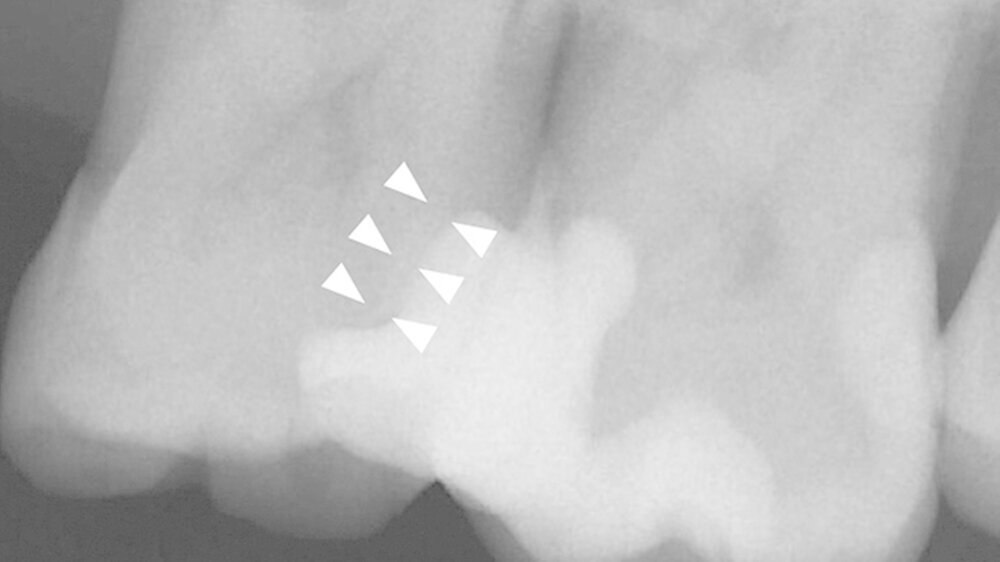

Ein 72-jähriger Patient stellte sich im Oktober 2013 zu einer Routinekontrolle in der Poliklinik für Zahnerhaltung und Parodontologie der Universität Regensburg vor. Bei der Befunderhebung wurde aufgrund des Verdachts auf Approximalkaries eine Röntgenaufnahme im Bereich des zweiten Quadranten angefertigt. Im Bereich des Zahns 26 distal wurde eine "Caries profunda“ diagnostiziert (Abbildung 1) und daher ein Termin zur Füllungstherapie vereinbart.